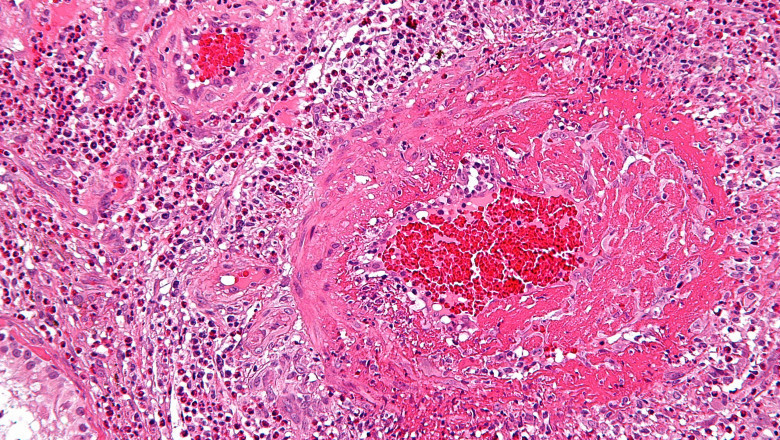

Small blood vessels become inflamed as a result of the illness known as microscopic polyangiitis (MPA). A unusual form of vasculitis, to be precise. Blood vessels may be harmed by the condition, which can also affect various body organs.

The body's blood is transported by blood vessels. Blood with oxygen is carried throughout the body through arteries from the heart. Small arteries branches are known as arterioles. Blood returns to the heart through veins. Small branching of veins are called venules. Microscopic Polyangiitis Market are the tiniest kind of blood vessels. These little blood tubes exchange nutrients and oxygen for waste.